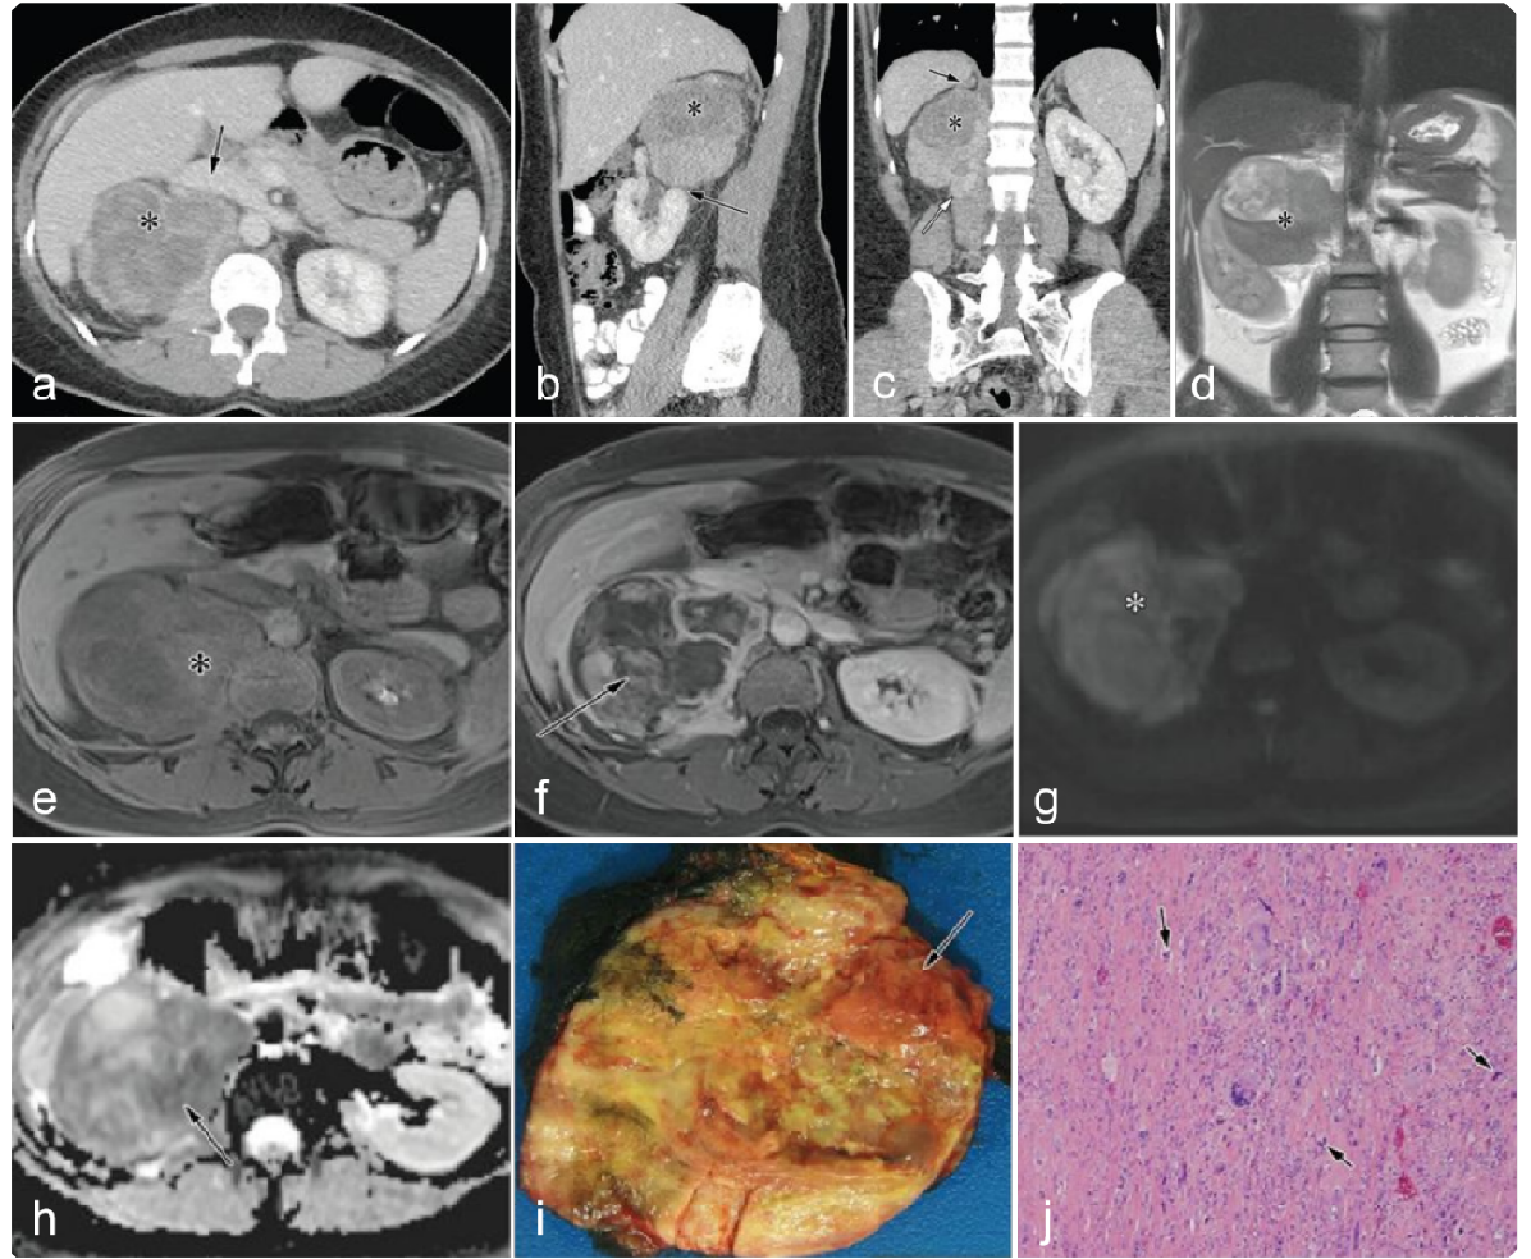

0a5fb18a3933294f8c258284440d05bf.png 病例 8:腹膜后(血管外)平滑肌肉瘤  46岁女性 腹膜后肿物不均质强化,病灶与前方下腔静脉、上方肾上腺及下方肾脏分界清晰,病灶侵犯右侧腰大肌。瘤内少量出血,不均质强化,弥散受限。大体病理显示瘤内出血、坏死;镜下:具有有丝分裂和核异型的梭形细胞。